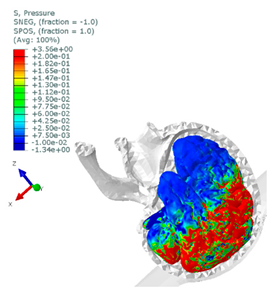

| Pedestrian accident—windshield impact at 72 km/h. The sustained injuries in brain tissues are assessed to be critical—cerebral contusion. |  50th-percentile male MB pedestrian model coupled with a FE compact car. |  Hydrostatic pressure in the brain [MPa]. |

| Motorcyclist—the helmet test according to ECE R22.05 (point B) with an advanced head model to compare HIC registered on the standard headform with cerebral pressure on FE model. |  EN 960 headform test published in Reference [50] (left): HIC = 1876 and amax = 213 g vs. the helmet with advanced head model (right—sagittal section through the head and helmet). |  Hydrostatic pressure in the brain [MPa]—sagittal section view, left hemisphere visible. |

- Acceleration, intracranial pressure, stress and strain, which have been postulated as head injury mechanisms and thereby may be used as predictions of various head injuries.

| Cerebral contusion | Intracranial pressure in region of interest (Coup) | 237 kPa |

| Intracranial pressure in region of interest (Contrecoup) | −104 kPa | |